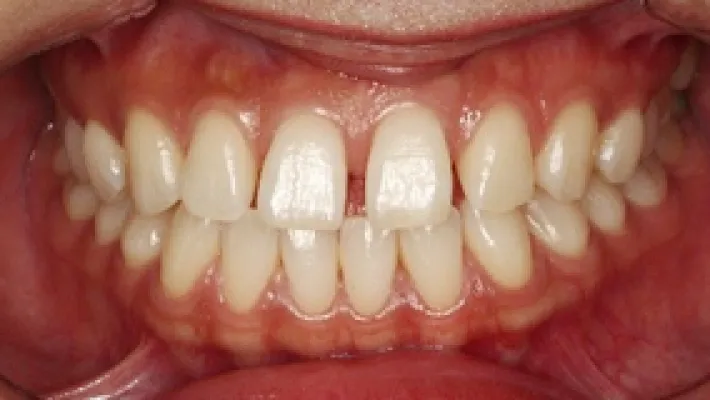

施術前

施術後

マウスピース矯正の部分矯正で上下前歯のすきっ歯を改善した症例です。

状態にもよりますが、すきっ歯はマウスピース矯正の得意とするケースの一つです。

効率的な治療計画で最小限の期間と負担で矯正を行いました。

矯正治療の期間・方法

矯正治療の期間や方法は歯並びや顎骨などの状態によって大きく異なります。

矯正治療は歯や歯周組織などに必ずダメージがあります。

矯正治療のダメージを最小限にするために健康的で現実的な治療計画を提案します。

治療費

583,000

治療期間

6.5ヶ月